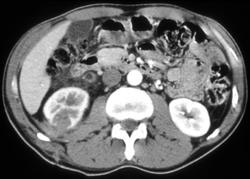

CASE NUMBER 20

Renal Laceration